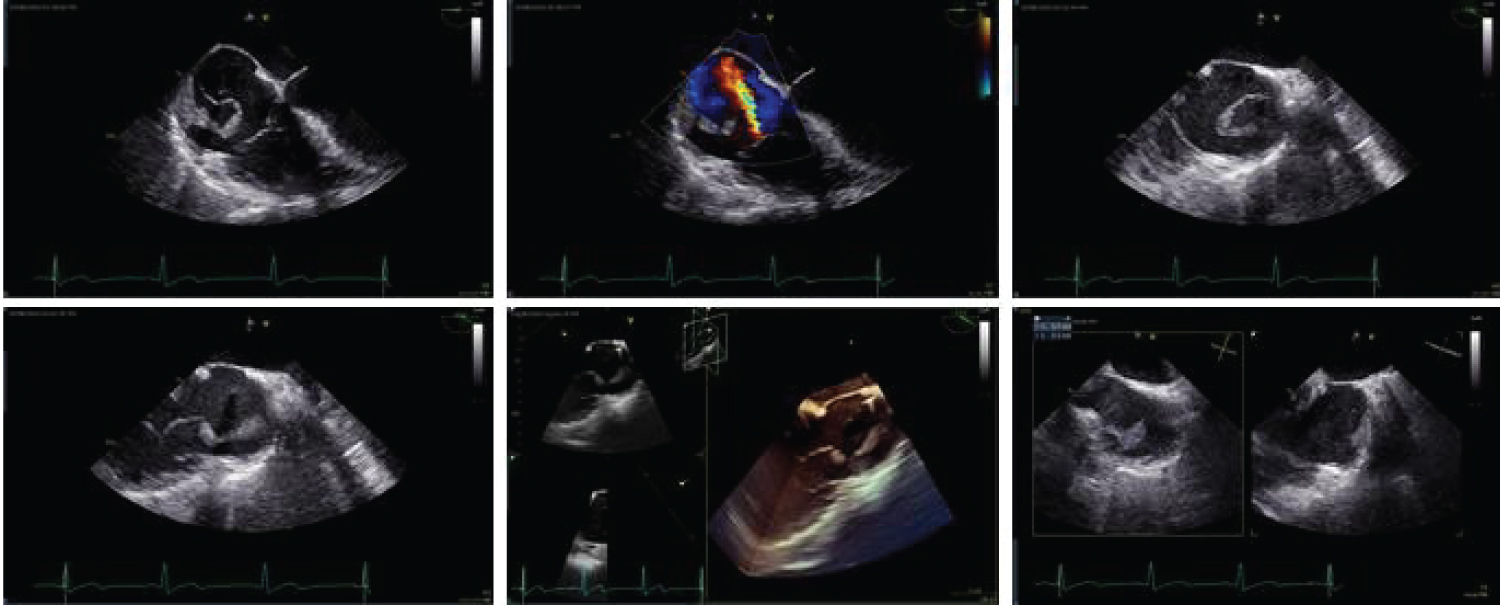

Upon arrival, the patient was noted to have a heart rate of 96 beats per minute as well as tachypnea at 24 breaths per minute (O2 saturation was 94% on 4 liters oxygen by nasal cannula). Physical examination was significant for bilateral rhonchi and expiratory wheezing; however, no audible murmurs, skin, nail, or eye lesions were observed. D-dimer was elevated at 6.28 μg/mL FEU and electrocardiogram demonstrated normal sinus rhythm with an incomplete right bundle branch block (Figure 1). Pulmonary computed tomography angiography was remarkable for scattered areas of hypo-attenuation within the segmental bilateral lower lobe pulmonary arteries, thought to be thromboembolic in nature. Subsequent transthoracic echocardiogram (TTE) revealed a large mass originating at the inferior vena cava (IVC) ostium and superior right atrial wall. The mass elongated into a highly mobile strand extending over 5.0 cm and prolapsing into the right ventricle during diastole (Figure 2).

For further characterization, the patient underwent a transesophageal echocardiogram (TEE), revealing a large homogenous mass measuring over 5.0 cm in length attached by a thick stalk to the superior right atrium and IVC junction. The mass prolapsed freely into the right ventricle in diastole (Figure 3). No other echocardiographic evidence of valvular heart disease was seen. Blood cultures drawn on admission remained negative and the patient remained afebrile throughout the hospital course.

Considering the echocardiographic findings, a heparin drip was initiated to prevent thromboembolic complications. Cardiothoracic surgery and cardiology were consulted. A multidisciplinary team decision to perform a percutaneous vacuum-assisted thrombectomy with the AngioVac device and venous chemo-port removal was made. An AngioVac cardiotomy resection of the right-sided intracardiac mass was performed utilizing venous-venous extracorporeal membrane oxygenation (ECMO) cardiopulmonary bypass under fluoroscopy and TEE guidance. The mobile portion of the mass was removed, accounting for approximately 80% of the lesion (Figure 4). The sessile portion of the mass was unable to be extracted with the AngioVac system, as it brushed against the right atrial wall. Pathology results demonstrated decolorized thrombus with focal features of an early organization. There were no intra- or post-procedural complications and the patient was discharged on dabigatran for anticoagulation.